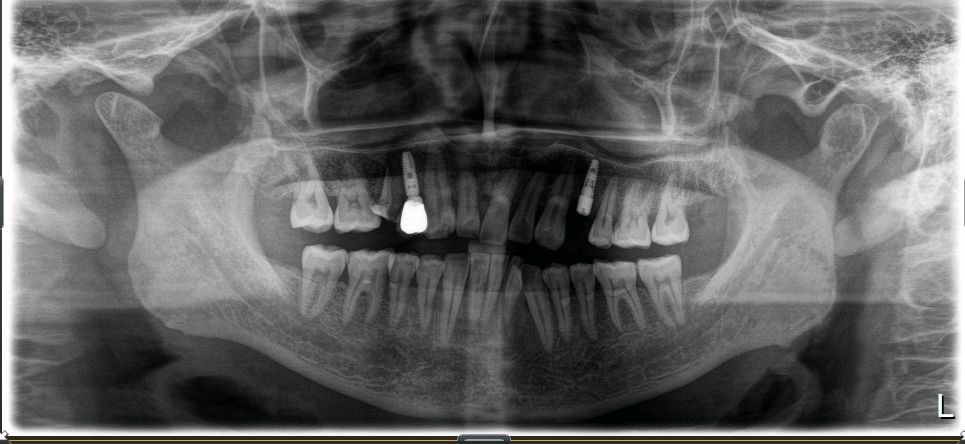

术中全景片